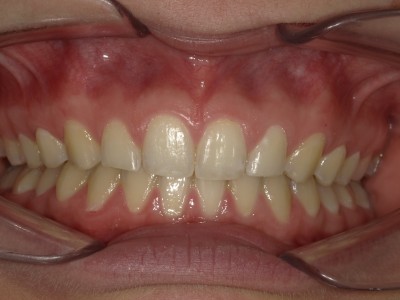

Retentie: Wrap + C-C bar onderkaak